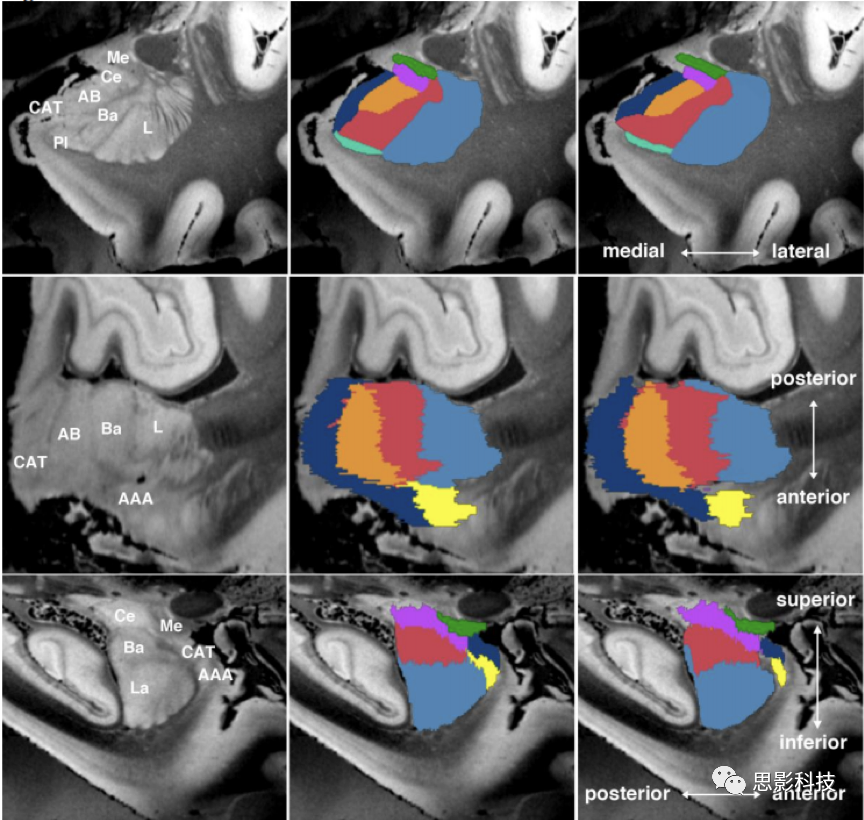

2.杏仁核亞區(qū)分割與體積分析。主要包括:杏仁核亞區(qū)的分割;杏仁核亞區(qū)的體積提?。恍尤屎梭w積的統(tǒng)計檢驗。

圖示杏仁核亞區(qū)分割